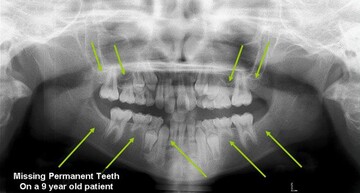

Hypodontia (the common dental term) describes a situation when fewer than 6 permanent teeth are missing, the term Oligodontia is used when more than 6 permanent teeth are missing (they were never formed). The most common missing teeth are the third molars (otherwise known as the Wisdom Teeth), followed by the premolars and the lateral incisors. Although it is not uncommon to have one missing tooth, patients with multiple missing teeth generally have a strong genetic component and it has been linked to conditions such as Ectodermal Dysplasia and several syndromes. Because early recognition aids in proper treatment, your dentist will refer you to specialists (orthodontist, oral surgeons, etc) that will determine which options suit you best to replace the missing teeth.